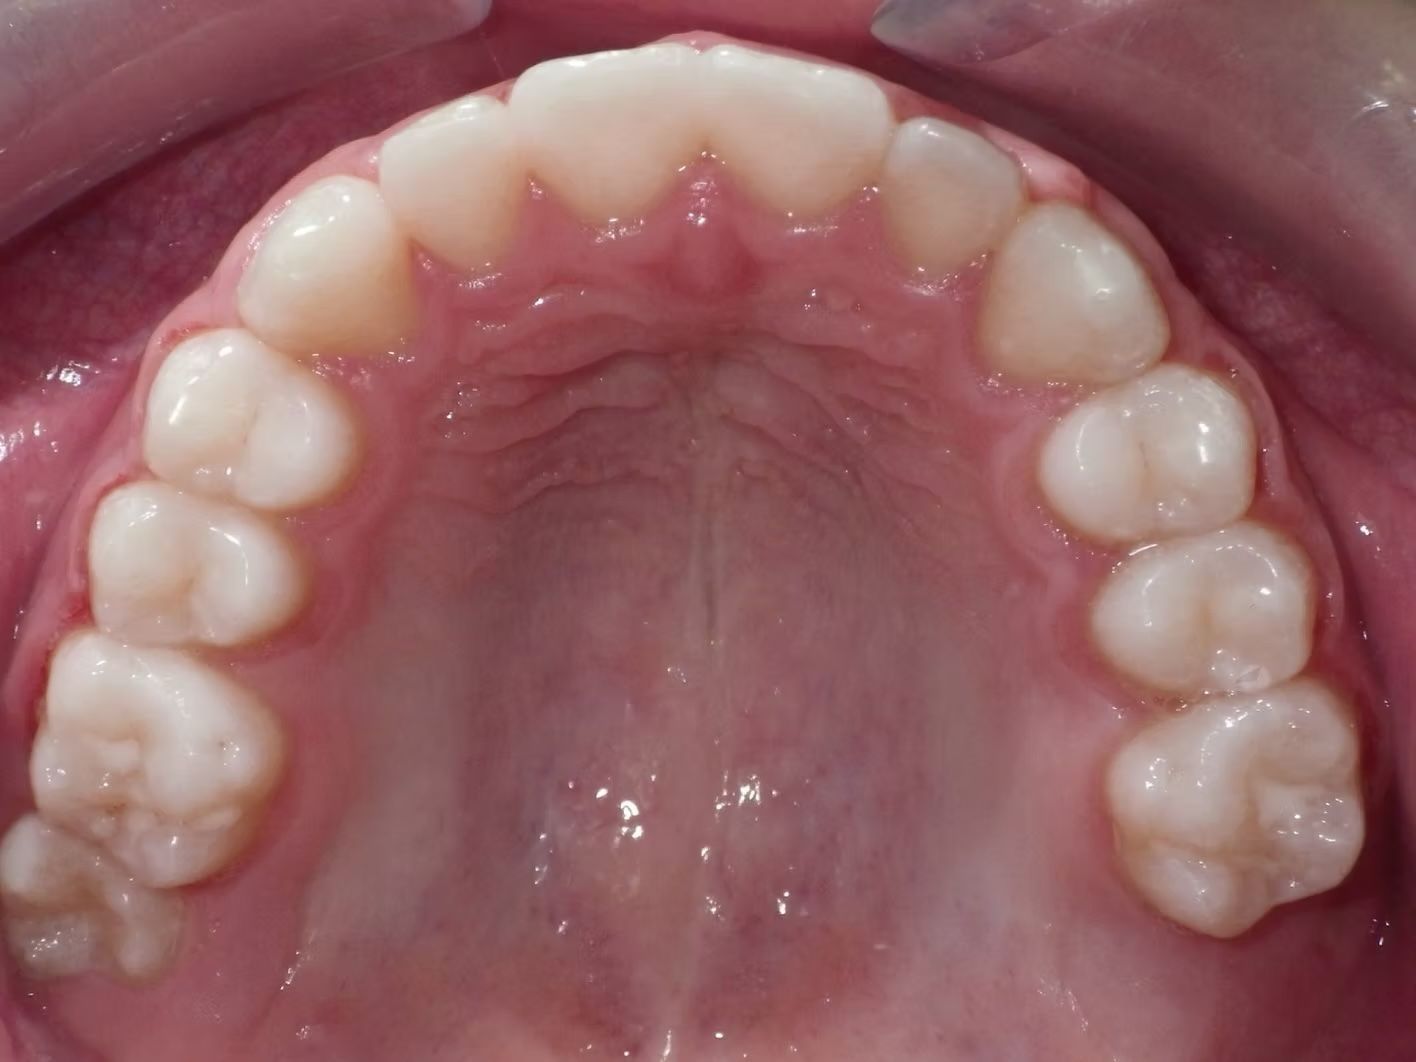

Imset

Imset came to see Dr. Bret because he felt like the upper and lower teeth were too crowded. The lower canines were in cross-bite with the upper teeth and there was significant crowding in the lower arch. He previously had 2 teeth pulled in the top and at the time none in the bottom. This made the top jaw smaller than the lower and the lower teeth didn't have room to fit inside the top teeth. We had 2 lower teeth extracted, and then aligned the upper and lower teeth to fit excellently together- no more crowding!